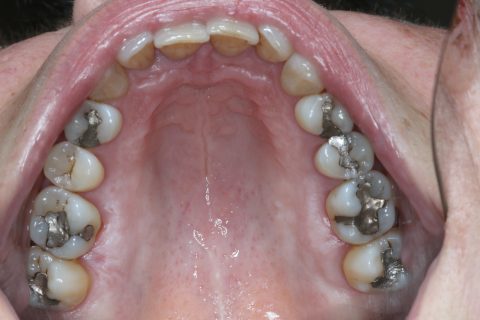

Amalgam

| Vorteile | vertetbarer Preis, sofort herstellbar, leicht zu verarbeiten |

| Nachteile | nicht zahnfarben, dunkel gibt ständig hochgiftiges Quecksilber ab |